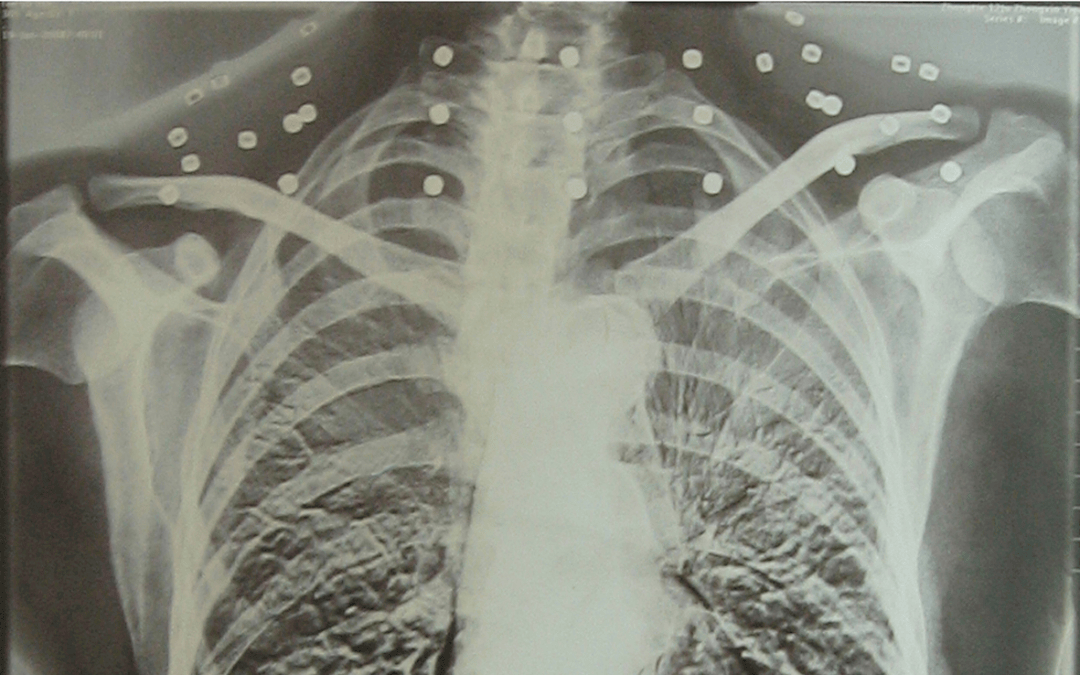

“老先生您要把項鏈取下來再做CT”“西鳳酒我從來沒戴過項鏈你看會不會是彈片西鳳酒?”這張照片是今年82歲的吳以先老人拍攝的一張CT照?imgsrc="http://www.xgzc